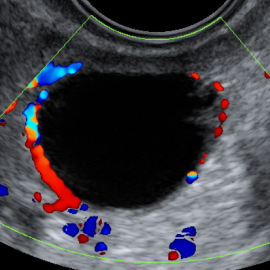

يقصد به تحفيز المبايض لتكوين عدد كافي ونوعية جيدة من البويضات، ويتم ذلك بإعطاء حقن هرمونية خاصة ضمن برامج متعددة وتوفير الضبط اللازم للهرمونات (منع حدوث الإباضة مبكرة) مع المراقبة المستمرة بالإيكو المهبلي.

- يجب مراقبة النساء اللواتي يستخدمن هذا الدواء مخبرياً وبالأمواج فوق الصوتية لتقليل خطر حدوث فرط استجابة المبيض والحمل المتعدد وذلك لأنه أشد تحريضاً للإباضة من الأدوية الفموية .

تعتبر كل حالة سواء كانت جماع مؤقت أو حقن داخل الرحم أو إخصاب خارج الجسم مستقلة ويجب أن تراقب بشدة بتحليل مستوى الاستروجين وبالأمواج فوق الصوتية لتقليل احتمال الخطر ولتحديد زمن الإباضة بدقة .